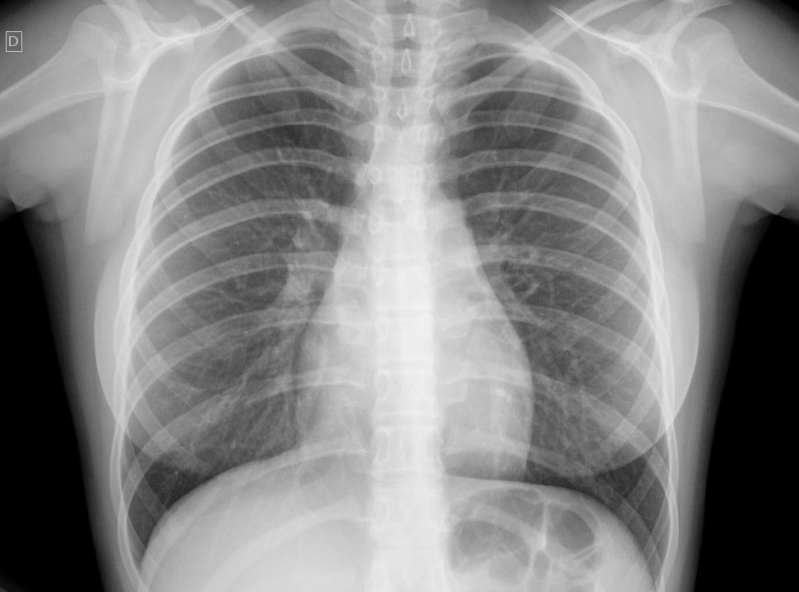

Impressora para Raio-x

RS IMPRESSORASUma impressora para raio-x deve ser específica para que haja o perfeito resultado, principalmente, se houver algum incoveniente que necessita de tratamento. Esse tipo de equipamento é...

Uma impressora para raio-x deve ser específica para que haja o perfeito resultado, principalmente, se houver algum incoveniente que necessita de tratamento. Esse tipo de equipamento é imprescindível em hospitais e clínicas.

Para uma peça de excelência, é de extrema autoridade contar com a ajuda de profissionais especializados e aptos a expandir um serviço de particularidade.

Deseja mais informações sobre impressora para raio-x?

Desenvolvendo um trabalho que oferece comodidade e certificando soluções inovadoras em outsourcing de impressão, a RS Impressoras é consolidada em seu segmento por conta da excelência apresentada em seus serviços.

Priorizando sempre as necessidades dos seus clientes, a empresa conta com uma equipe de profissionais elevadamente qualificados e aptos a expandir um serviço completo e de extrema particularidade.

Com experiencia a começar de 2007, a RS Impressoras garante a satisfação dos seus solicitantes, procurando sempre melhorias em cada um dos seus processos. Saiba mais entrando agora mesmo em contato!

Uma impressora para raio-x deve ser específica para que haja o perfeito resultado, principalmente, se houver algum obstáculo que necessita de tratamento. Esse tipo de equipamento é imprescindível em hospitais e clínicas.

Para uma peça de excelência, é de extrema seriedade contar com a ajuda de profissionais especializados e aptos a ampliar um serviço de particularidade.

Deseja mais informações sobre impressora para raio-x?

Desenvolvendo um trabalho que oferece comodidade e certificando soluções inovadoras em outsourcing de impressão, a RS Impressoras é consolidada em seu segmento por conta da excelência apresentada em seus serviços.

Priorizando sempre as necessidades dos seus clientes, a empresa conta com uma equipe de profissionais elevadamente qualificados e aptos a ampliar um serviço completo e de extrema particularidade.

Com experiencia doravante 2007, a RS Impressoras garante a satisfação dos seus solicitantes, procurando sempre melhorias em cada um dos seus processos. Saiba mais entrando agora mesmo em contato!